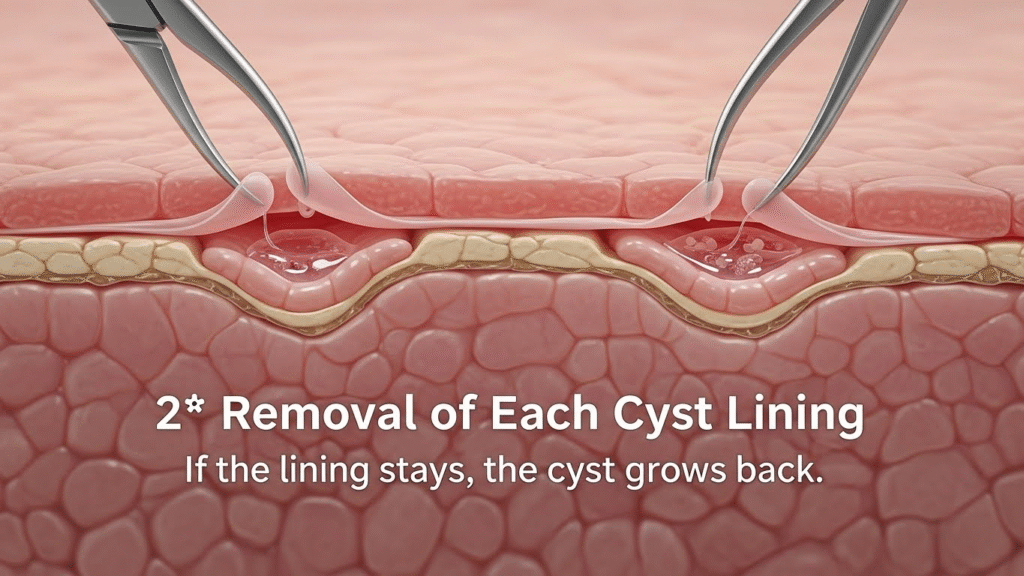

2️⃣ Removal of Each Cyst Lining

If the lining stays, the cyst grows back.